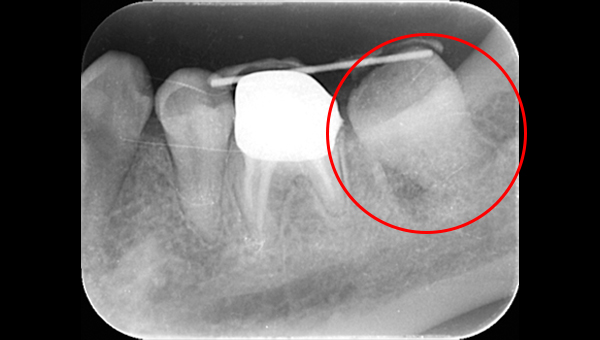

CT像①

CT像②

説明:

CT像です。根の中央を超えて虫歯が広がっているのがわかります。そこに上の親知らずを移植することに

しました。